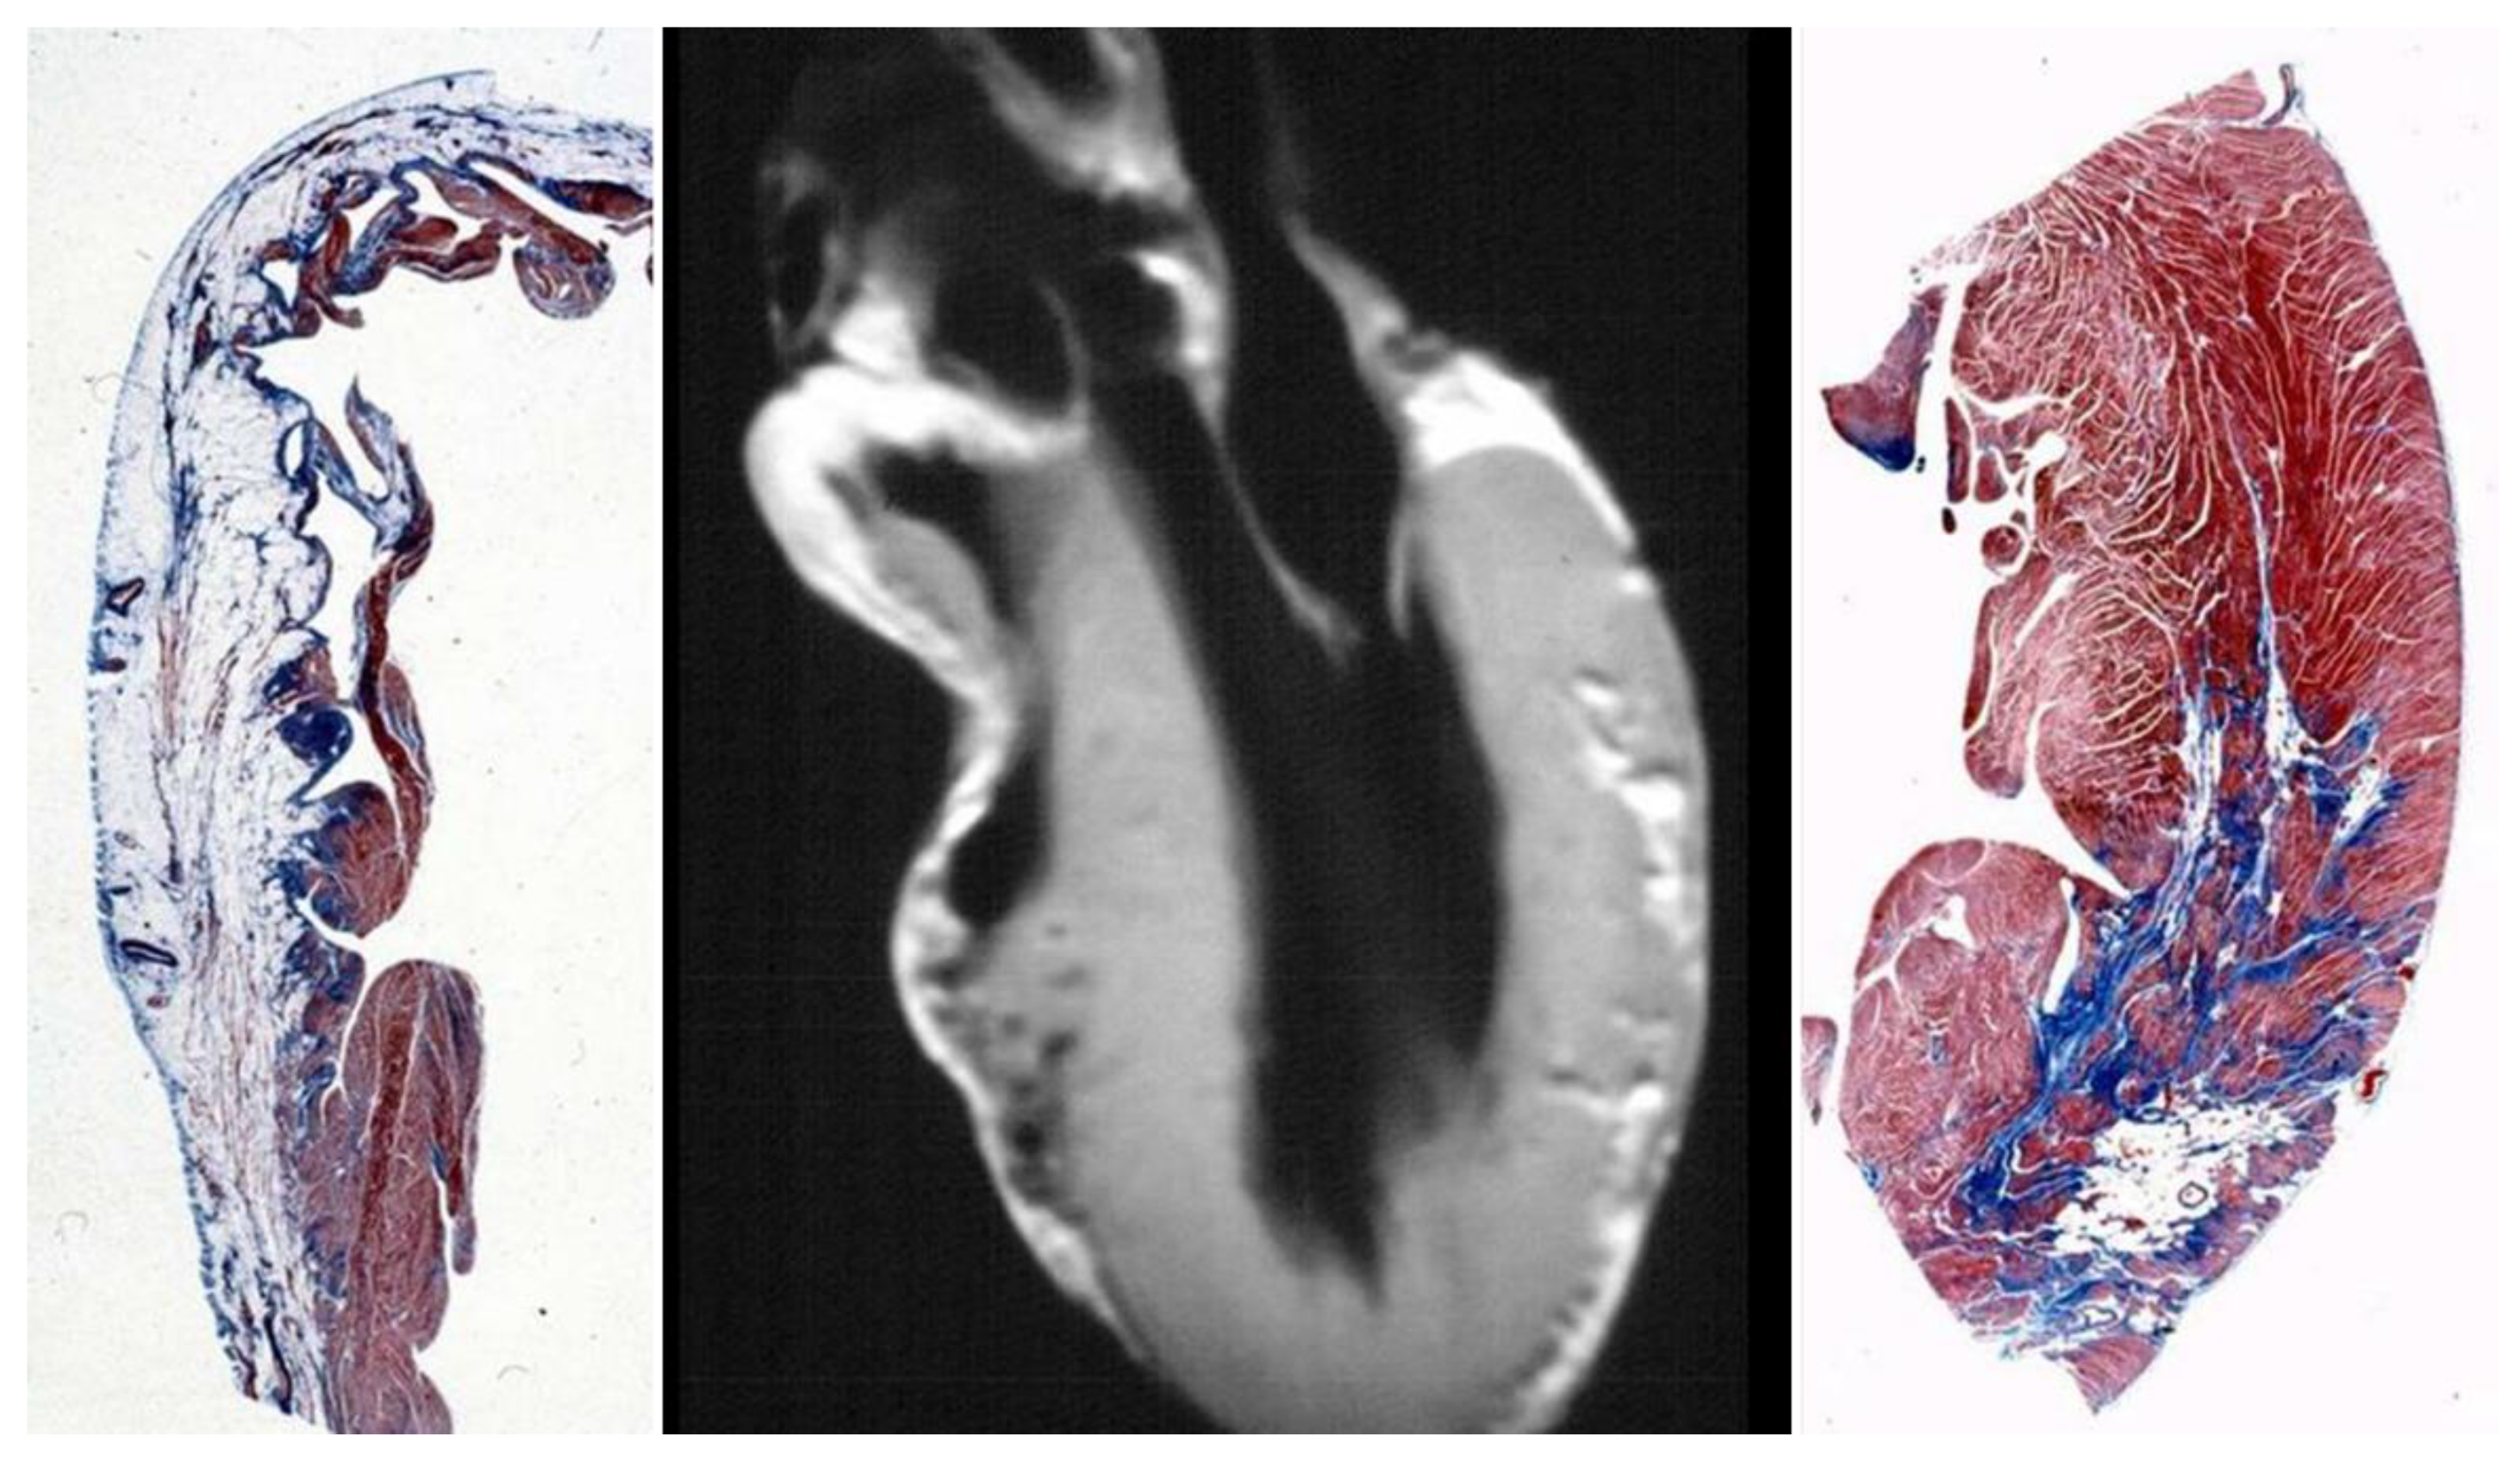

4. Pathological Substrates